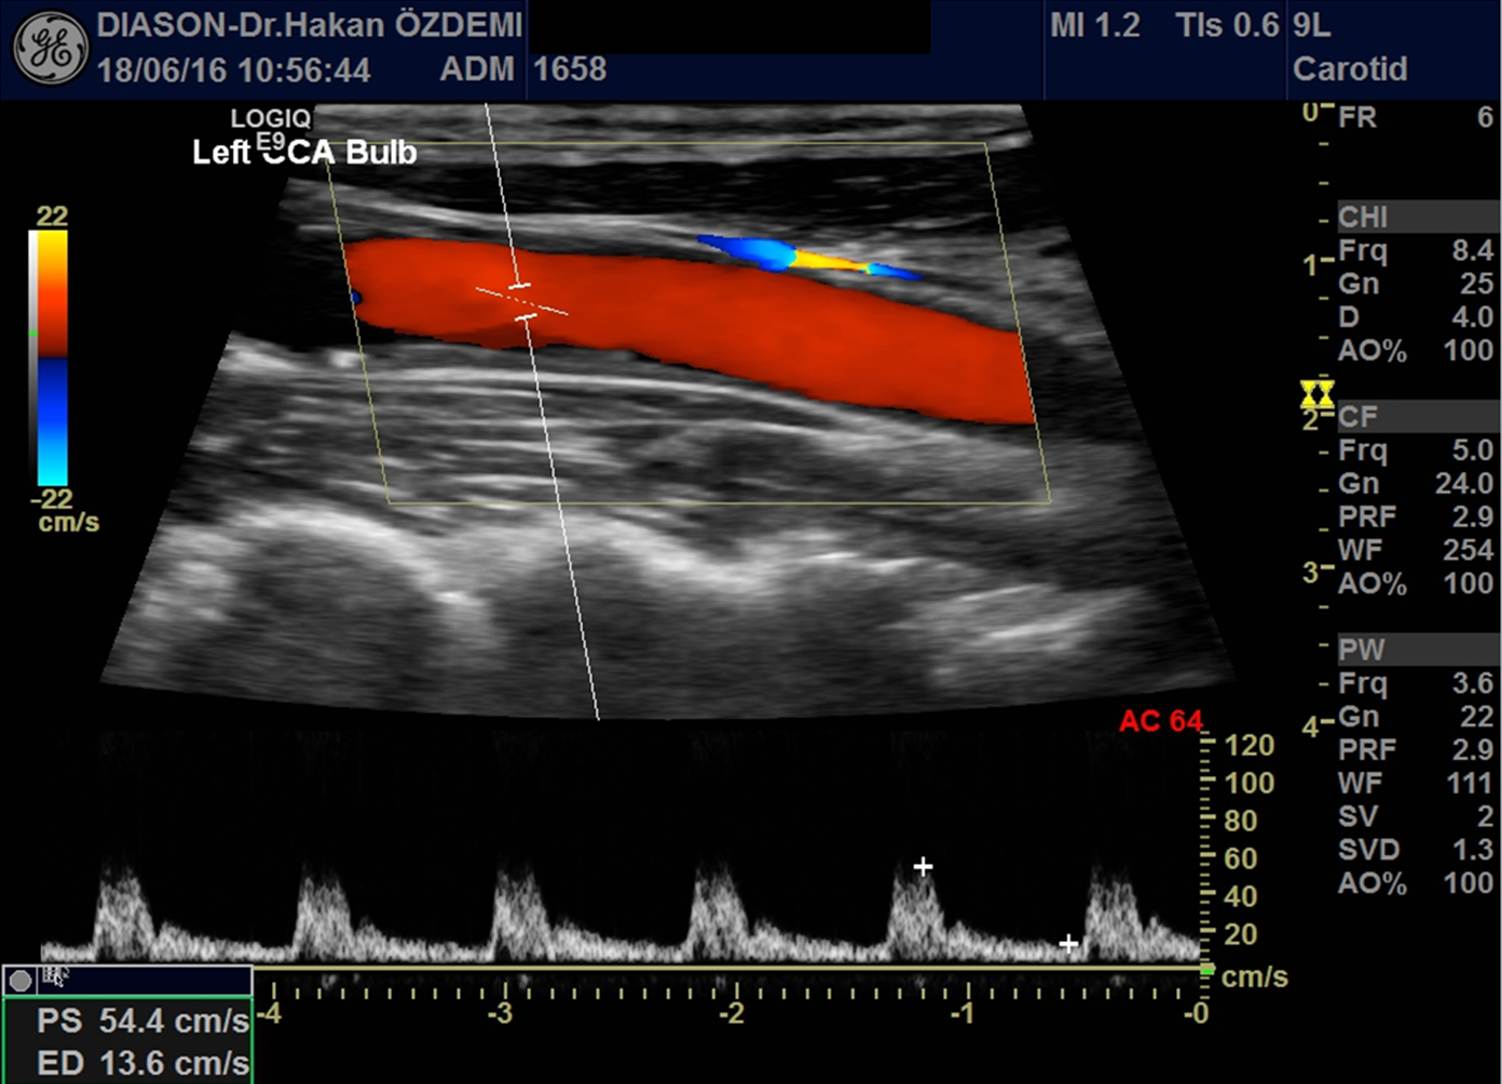

KAROTİS VE VERTEBRAL ARTER (BOYUN DAMARLARI) RENKLİ DOPPLER ULTRASON

Boyun bölgesinde yer alan, beyin ve beyinciği besleyen damarlar incelenir.